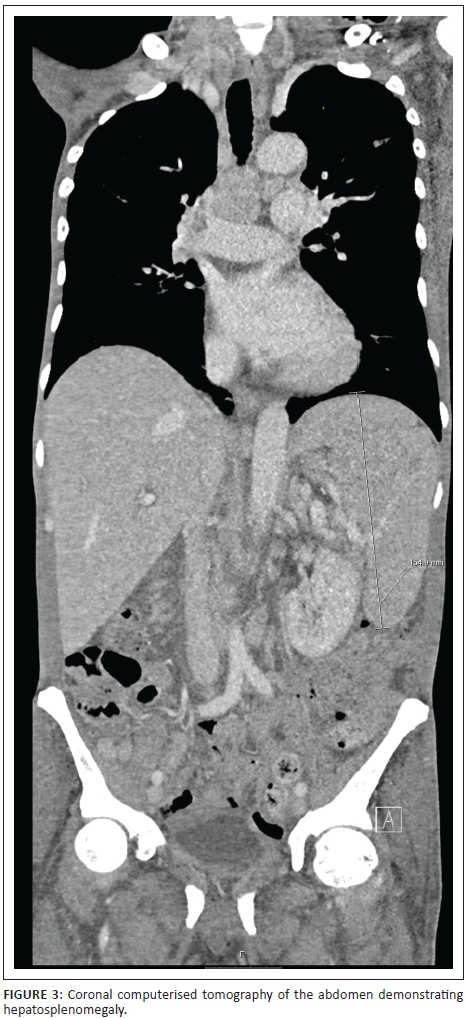

A chest radiograph demonstrated right basal opacification. Computerised tomography of the chest abdomen and pelvis (CT-CAP) revealed patchy air space opacification at the left oblique fissure, left lower and right lower lobes, paraseptal and central lobular emphysema and bibasal atelectasis (Figures 1 and 2). Hepatosplenomegaly was confirmed and free fluid was evident throughout the abdomen and pelvis (Figure 3). Multiple enlarged lymph nodes (up to 1.8 cm diameter) were visualised throughout the thorax, abdomen and pelvis (Figures 4 and 5).

Widespread homogenous lymphadenopathy may be a feature of both MAC and HL; however, lymphadenopathy is often massive in HL (> 3 cm diameter).5 Hepatosplenomegaly is commoner in MAC than in HL.5 HL tends to be seen with a CD4 count around 240 cells/μL4; in contrast, disseminated MAC is typically found with CD4 < 50 cells/μL.1